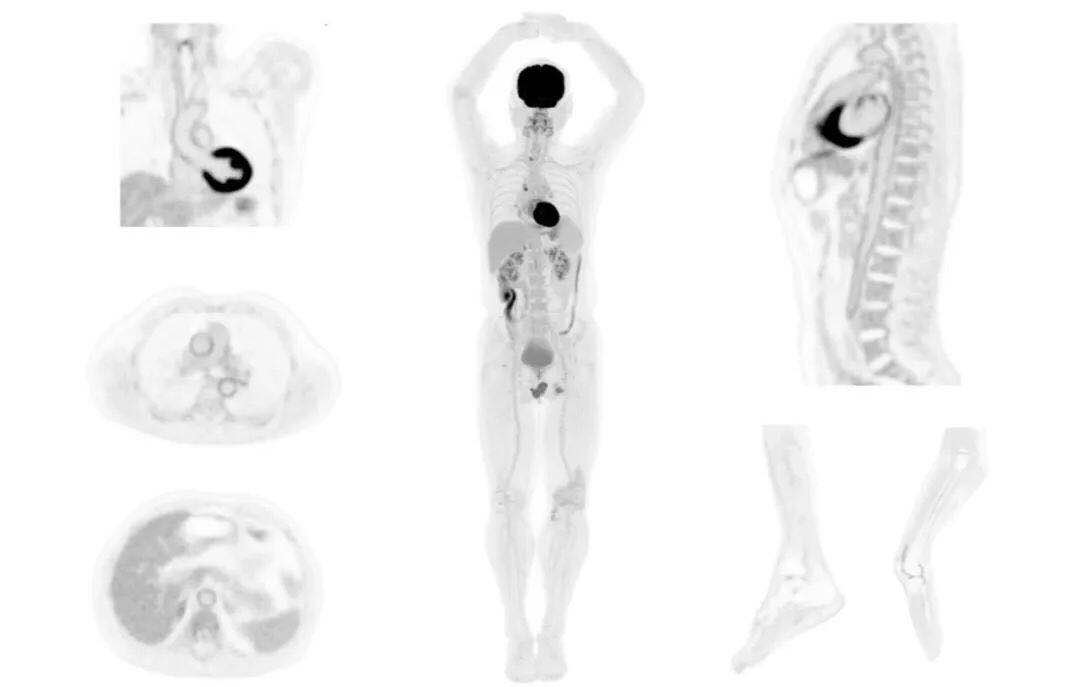

uExplorer探索者不再局限于傳統(tǒng)靜態(tài)代謝過(guò)程3D成像,而是在此基礎(chǔ)上新增一個(gè)維度——時(shí)間,從而實(shí)現(xiàn)4D全景成像。

注射總劑量為7.8mCi,14分鐘全身采集時(shí)間,在擁有超高靈敏度與超高分辨率的uEXPLORER上,即可得到展示顯示人體諸多精細(xì)結(jié)構(gòu)的高清三維圖像。

注射總劑量為7.8mCi,注射后1.6小時(shí),基于uEXPLORER探索者掃描1分鐘的圖像

注射總劑量為0.67 mCi FDG(低于常規(guī)劑量的十分之一),基于uEXPLORER探索者掃描15分鐘的圖像

注射總劑量為6.9mCi,注射后10小時(shí),基于uEXPLORER探索者掃描14分鐘的圖像